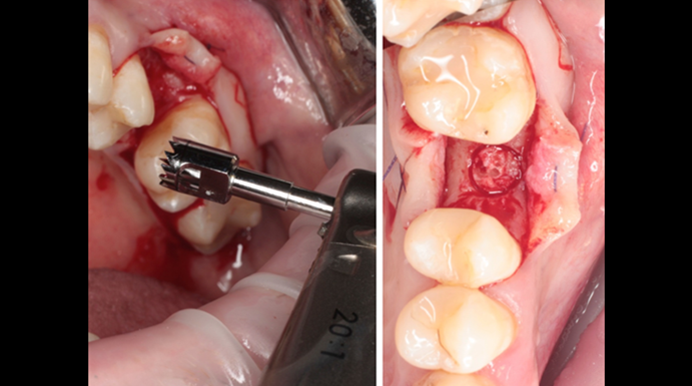

Clinical case: Ridge splitting technique using SmarThor + AnyRidge as expander

- Courtesy of Dr.Kwang-Bum Park, Korea -

AnyRidge, ridge splitting, GBR, Dr. Kwang-Bum Park, mandibular posterior, SmartThor, Mega-Oss, thin ridge, bone regeneration

AnyRidge implant system. SmarThor, Mega-Oss